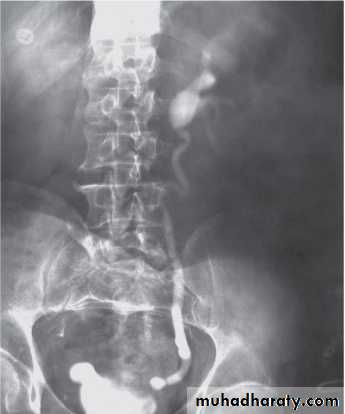

The VCUG:

the definitive examination

to diagnose and grade reflux and establish reversible causes

must include a voiding phase:

in some cases, reflux may be seen only during the elevated intravesical pressures associated with micturition.

in visualizing the urethra, may allow the diagnosis of outflow obstruction to be made (e.g., posterior urethral valves).

MCUG